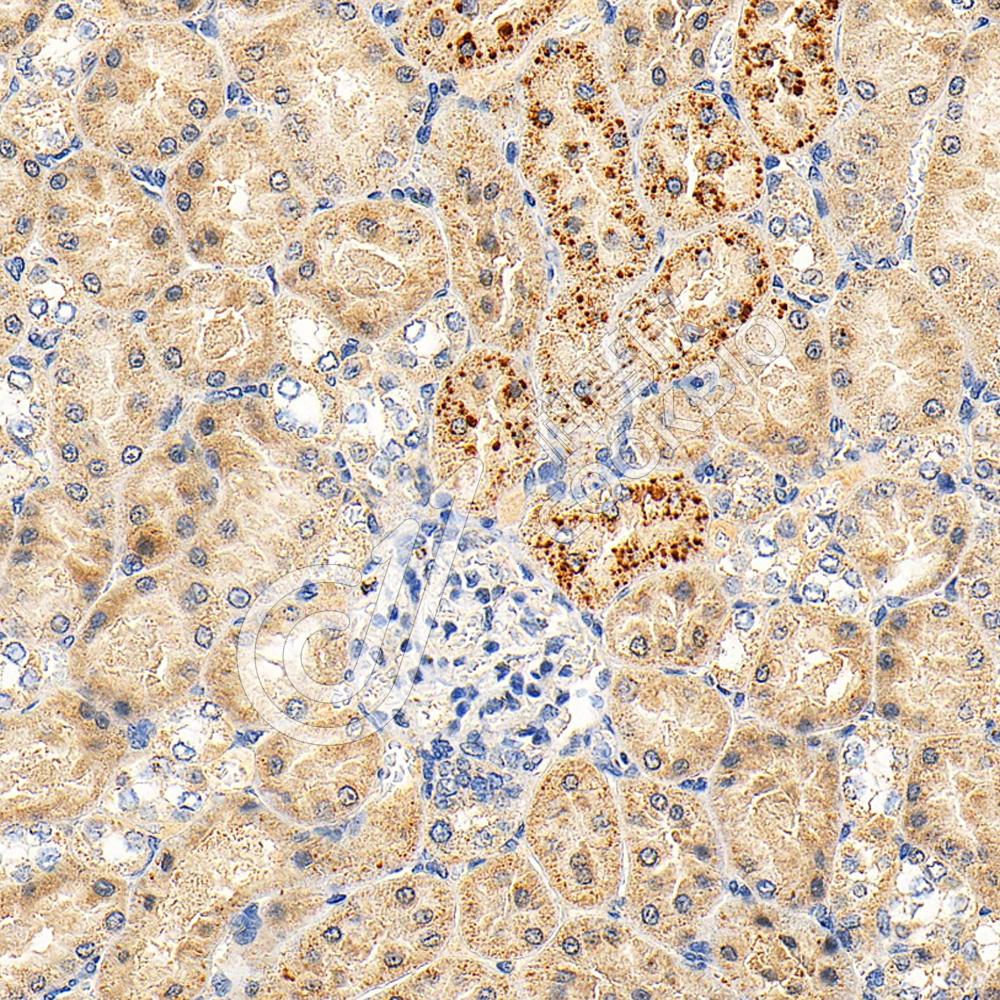

IHC检测IL-2 Receptor alpha蛋白(货号 K134836).

样品: 小鼠脾, 4%多聚甲醛 (货号KSG1101) 固定12-24小时.

抗原修复: 柠檬酸抗原修复液(干粉, pH 6.0) (KSG1201), 98℃, 20分钟.

—抗: 1: 600稀释, 4℃ 孵育过夜.

二抗: S-vision免疫组化多聚二抗(山羊抗兔),即用型 (货号KB3906), 室温孵育20分钟.